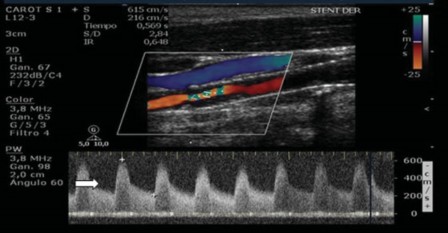

Stanziale y col. reportan resultados similares, determinando como estenosis mayor al 50% un punto de corte de VPS de 230 cm/seg y mayor al 70% un pico sistólico de 350 cm/seg, con una especificidad mayor al 95% para ambos.18 Esa última es la escala que utilizamos en nuestra institución (►Fig. 9).

El EDC detectó una zona de aliasing y en el modo espectral se observa flujo turbulento, tipo "jet," con pérdida de la ventana espectral y se registró VPS y VFD (615 cm/seg y 216 cm/seg), comportándose como una estenosis significativa >70% según Stanziale y col.